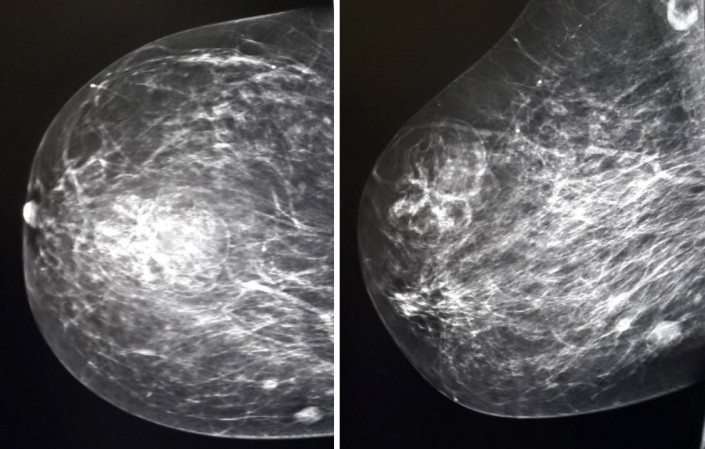

"Первый конкурирующий диагноз, который выставляется пациенткам, - это рак молочной железы или объемное образование, BI-RADS 4", - пишут исследователи.

Как пишут авторы исследования, выявить эхинококкоз в груди помогла информация о наличии этого заболевания ранее. В обоих же случаях болезнь "скрывалась" под видом рака молочной железы. При этом на маммограммах патология не укладывалась в классическую картину патологических состояний (рак, киста, фиброаденома, филлоидная опухоль). Также врачи отмечают, что в обоих случаях образования были безболезненными при пальпации.